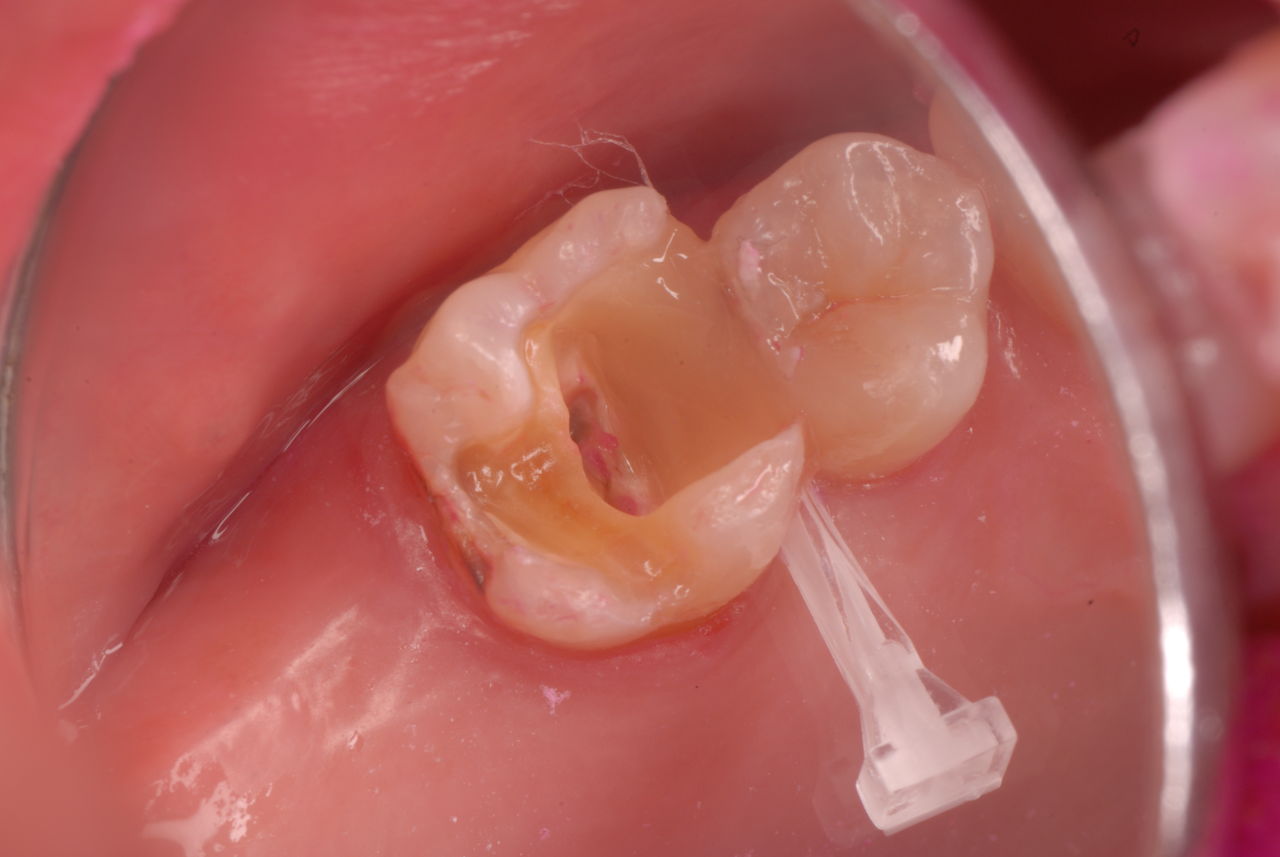

入れ歯の話から入りました。色々不満で注文があるようです。でも話が一段落して口腔内を調べると殆どの歯が重症で抜けそうな歯だらけなのです。

ご自分でやられても歯茎から血が出ないと話をされていましたが、私がブラシを当てると悲惨な状態であることがわかりました。

何故歯が悪くなるのか、歯周病で抜けるのか分からなければ何を入れても歯は悪くなり抜けていくのです。